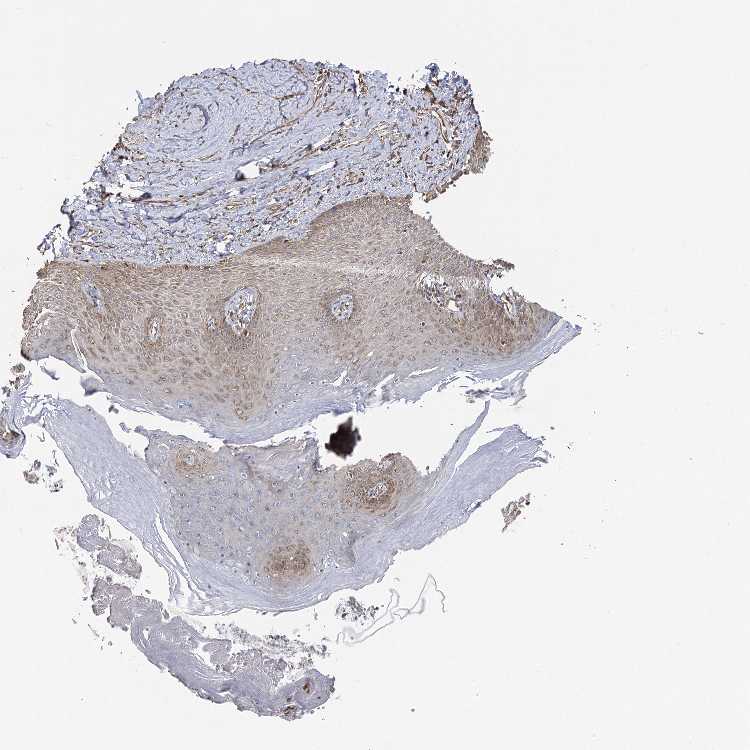

SKIN 1 - Antibody stainingi

Antibody staining in the annotated cell types in the current human tissue is reported as not detected, low, medium, or high, based on conventional immunohistochemistry profiling in selected tissues. This score is based on the combination of the staining intensity and fraction of stained cells.

Each image is clickable and will lead to virtual microscopy that enables deeper exploration of all samples and also displays staining intensity scores, fraction scores and subcellular localization as well as patient and tissue information for each sample.

Antibody HPA013162Antibody HPA036652Antibody CAB032830

Langerhans Medium-Medium

Cells in basal layer -Medium-

Cells in corneal layer -Not detected-

Cells in granular layer -Medium-

Cells in spinous layer -Medium-

Eccrine glands -Medium-

Endothelial cells -High-

Extracellular matrix -Not detected-

Fibroblasts Not detected-Medium

Fibrohistiocytic cells -High-

Hair follicles -Medium-

Keratinocytes Medium-Medium

Langerhans cells -Medium-

Lymphocytes -High-

Melanocytes LowHighHigh

Sebaceous glands -Medium-

Vascular mural cells -Not detected-